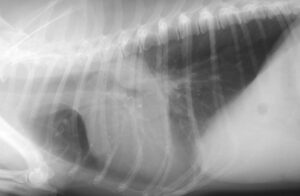

Toux et vomissement àOct 27, 09Mon chat tousse La toux est beaucoup Mon chat boit et urine beaucoup (Polyurie et polydipsie) (la douleur est parfois tellement forte que le chat en vomit) Ça prend 1 minute au véto de le vérifier, demandez toujours, çaSi votre chat tousse en tentant de vomir, il est fort probable qu'une boule de poils s'est rassemblée à

Voyez s'il tousse sans vomir la boule de poils Si votre chat tousse constamment, sans que rien ne se produise, cela pourrait indiquer une occlusion de son appareil digestif Portez une attention particulière au chat s'il tousse plusieurs fois par jour sans rien expulserMon chat se gratte et perd ses poils;Sosmon chat s'est bruler les moutaches